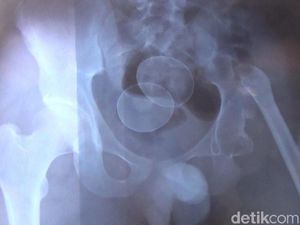

Cerita Akmal, Mengaku Bertelur hingga Dinyatakan Alami Gangguan Jiwa

Pihak kepolisian akhirnya menyatakan Akmal mengalami gangguan jiwa. Hal itu terkait pengakuannya bisa bertelur dari anusnya.